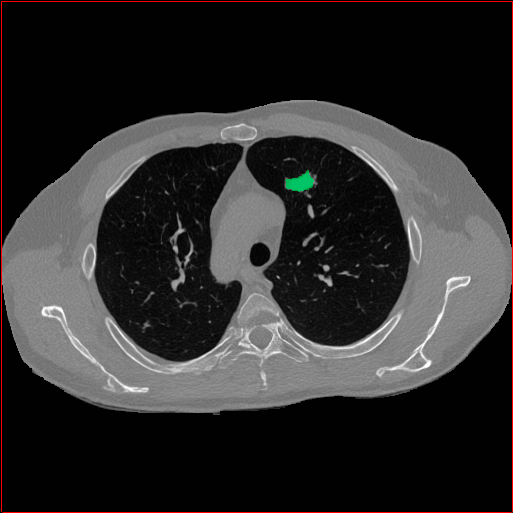

Lung Tumor

0.75×0.75×0.60.75\times 0.75\times 0.6

mm

512×512×512512\times 512\times 512

Figure 4: MAISI-v2 segmentation-guided results for five types of tumors. We show results for different voxel spacing and volume size to demonstrate the flexibility of MAISI-v2. Different Hounsfield Unit window is used to better show the contrast between tumor and normal tissues.